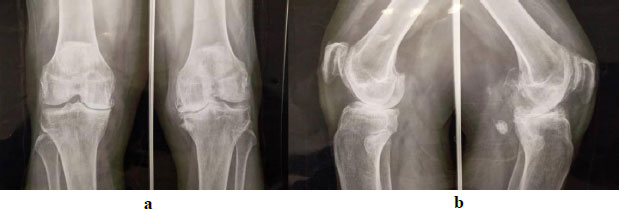

All patients exhibited advanced disease corresponding to stages IV or V (Fig. 2a,b). The full-length standing radiograph was performed in only three patients. The mean HKA angle was 171.35° ± 10°, indicating a mild global varus alignment of the mechanical axis of the lower limb.

Bilateral anteroposterior ( a ) and lateral ( b ) weight-bearing radiographs of the knees showing bilateral medial compartment osteoarthritis, more pronounced in the left knee associated with varus deformity, stage IV and V according to Ahlbäck.